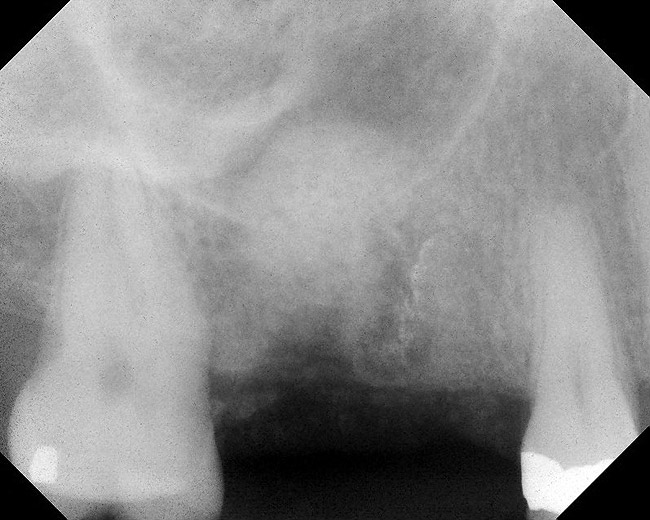

Figure 1  Buccal and radiographic views of posterior edentulism with significant sinus pneumatization in the molar region.

Figure 1

Figure 2  Buccal and radiographic views of posterior edentulism with significant sinus pneumatization in the molar region.

Figure 2